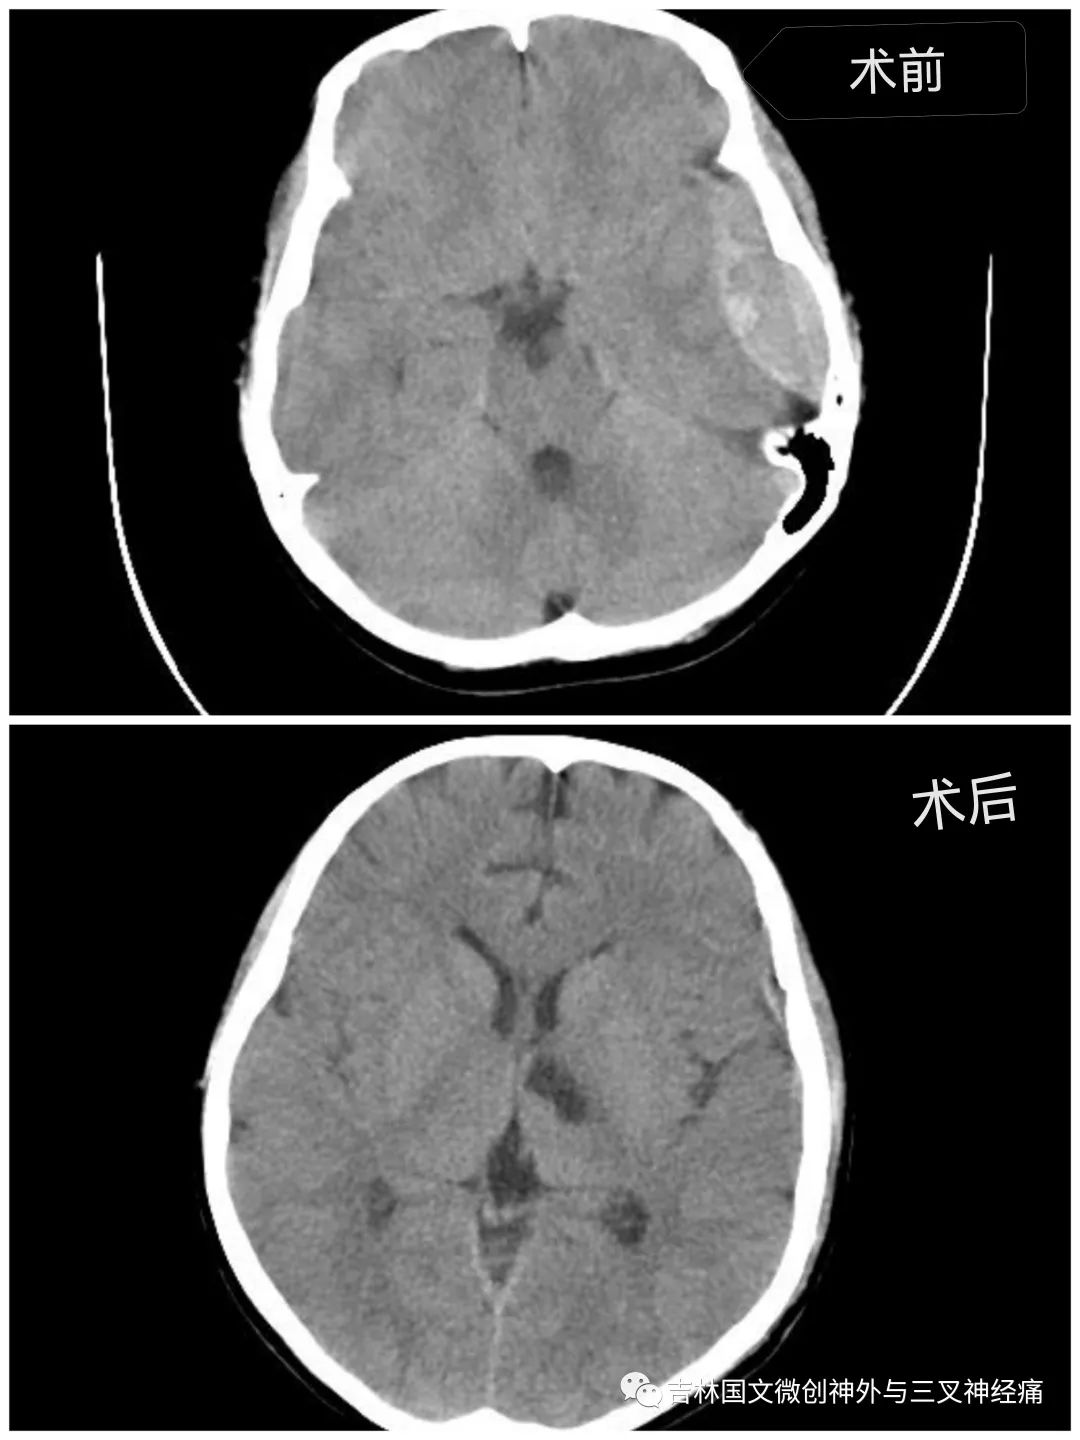

急促的車輪聲刺激著所有人的神經(jīng)。“孩子昏迷,顱內(nèi)出血量大,左側(cè)瞳孔散大,已腦疝,需要緊急診開顱手術(shù)”?!跗M主任向家屬交代著。家屬滿臉的焦急,并未有過多的猶豫,立即決定手術(shù)。從病人同意手術(shù)到進(jìn)入手術(shù)室,前后近用了20幾分鐘。

在王芃主任的帶領(lǐng)下,手術(shù)室的鼎力支持下,歷時近4個小時,手術(shù)順利完成。由于病人腦損傷很重,一直處于昏迷狀態(tài)。為了能讓孩子的未來不至于太自卑,少受一點損傷,少留下一道疤痕,王芃主任帶領(lǐng)他的團(tuán)隊用盡一切辦法在努力的保護(hù)病人的氣管(嚴(yán)重腦損傷、長期昏迷的病人,為了能保證呼吸道通暢,增加病人的活命幾率,一般都需要進(jìn)行氣管切開)。